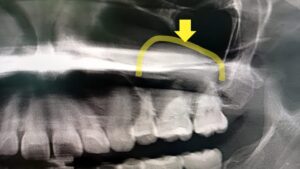

定期健診レントゲンで見つかった意外なものとはNew!!